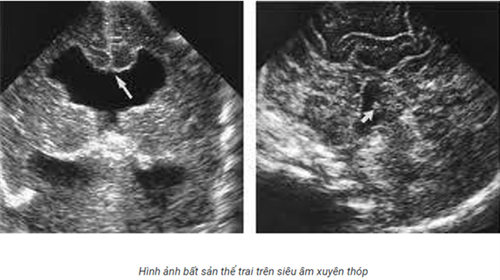

Siêu âm qua thóp là một trong những phương pháp chẩn đoán hình ảnh phổ biến nhất trong lĩnh vực y tế. Phương pháp này sử dụng sóng siêu âm để tạo ra hình ảnh của các cơ quan và mô trong cơ thể. Với khả năng xem được bên trong cơ thể một cách chi tiết và không xâm lấn, siêu âm qua thóp đã trở thành công cụ hỗ trợ quan trọng trong việc chẩn đoán và điều trị nhiều bệnh lý.

Siêu âm qua thóp là một phương pháp chẩn đoán hình ảnh sử dụng sóng siêu âm để tạo ra hình ảnh của các cơ quan và cấu trúc bên trong cơ thể. Thóp siêu âm là một thiết bị chuyên dụng được di chuyển trên da để tạo ra hình ảnh.